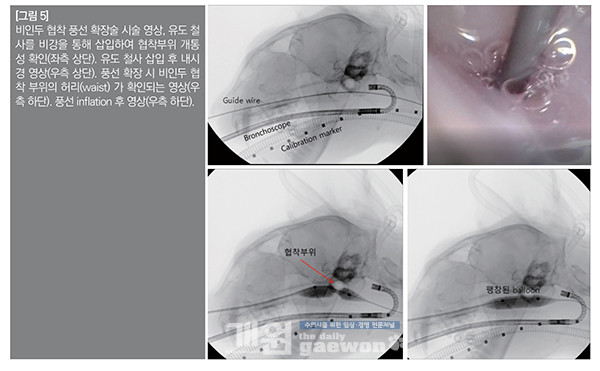

시술은 환자를 전신 마취한 후 내시경(retroflex pharyngoscopy)을 통해 협착부위를 확인하였는데, 일부 개통성이 있는 비인두 협착증이었다.

따라서 유도 철사를 비강을 통해 비인두로 삽입한 후에 CT 검사로 확인된 비인두 협착부위를 가운데 오도록 혈관 풍선을 삽입하였다. 삽입된 혈관 풍선을 총 5회 가량 inflation 시켰으며, 내시경을 통해 개통성을 확인하였다. 재협착을 막기 위해 비인두 협착부위에 mitomycin C를 점적하고, 약 5분 후 비강세척을 하고 종료하였다[그림 5].